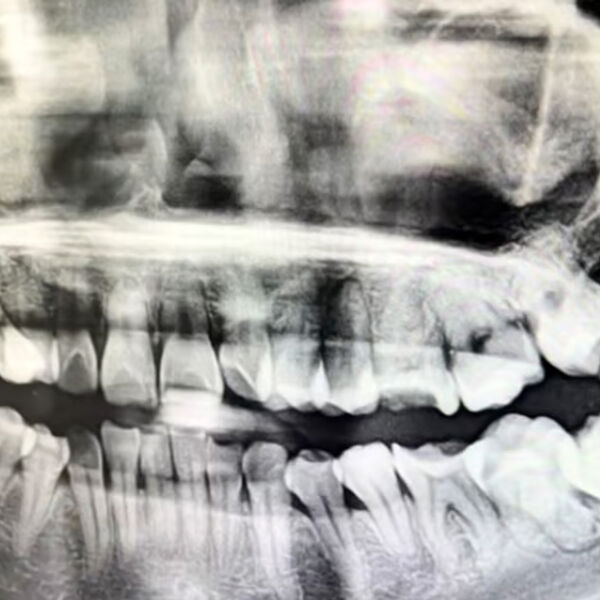

Китаянка не выжила после того, как врач по ошибке удалил ей здоровый зуб, сообщает SCMP.

По данным газеты, 12 марта 34-летней женщине из провинции Аньхой должны были провести операцию по извлечению зуба мудрости в городской больнице Аньцина. Однако стоматолог по ошибке удалил здоровый зуб, а затем насильно вставил его обратно, использовав проволоку.

Брат пострадавшей говорит, что операция длилась полтора часа и проводилась без анестезии. В результате у пациентки распухло лицо, а она сама стала испытывать невыносимую боль, которая со временем только усилилась.